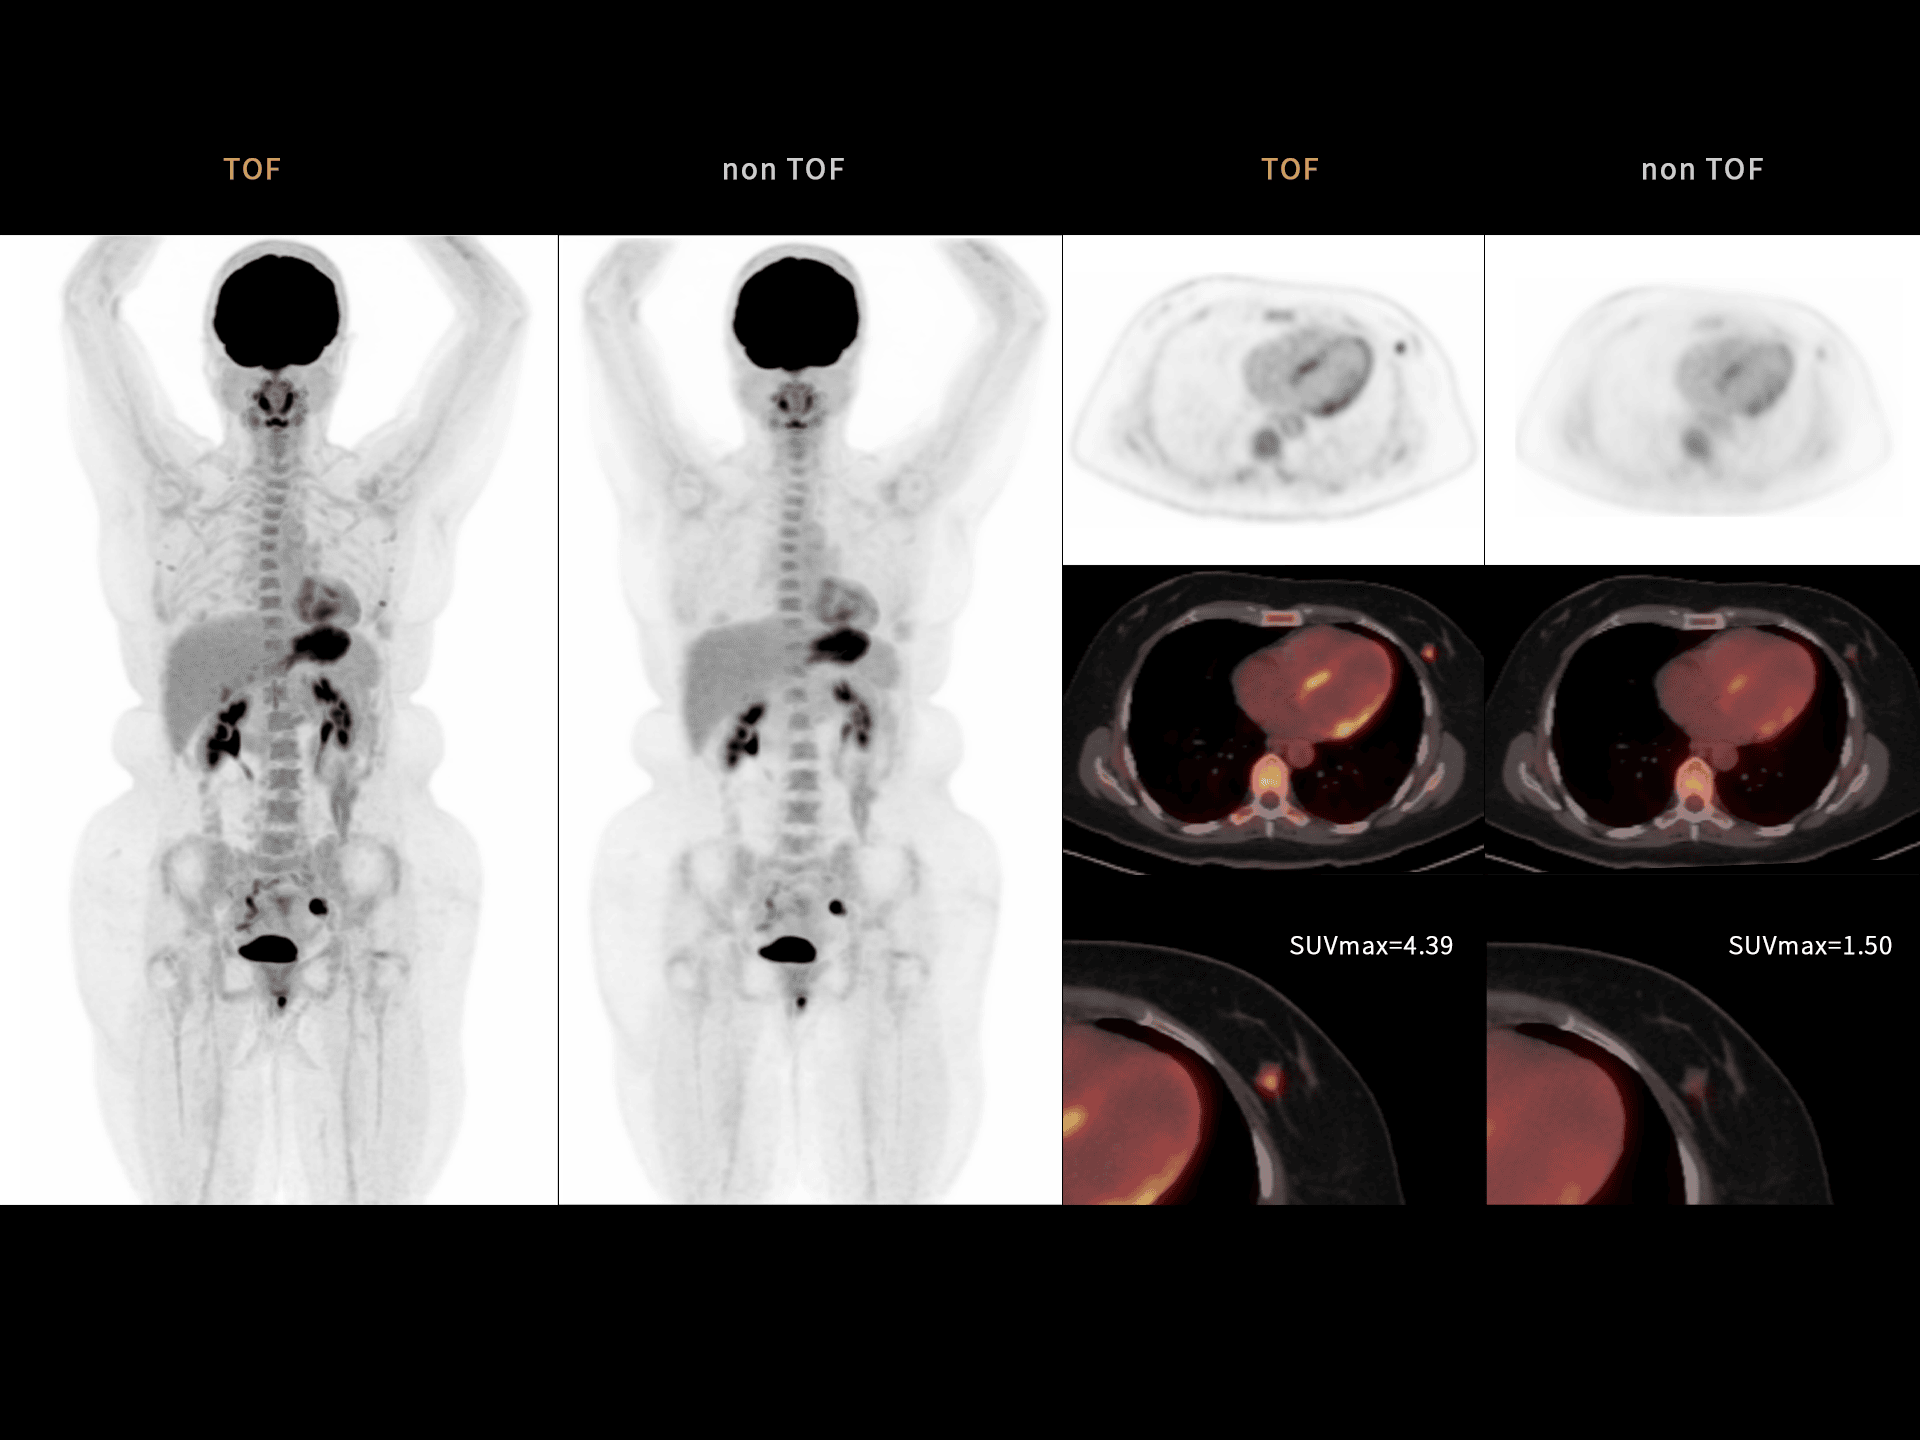

219 ps – rezoluție TOF de top

Rezoluția TOF de 219 ps crește claritatea imaginilor și detectabilitatea leziunilor mici, oferind un avantaj clinic major în diagnosticul PET/CT.

Rezoluție TOF de 219 ps pentru detecție precisă

Rezoluția TOF avansată de 219 ps îmbunătățește vizibilitatea leziunilor mici și acuratețea cantitativă.